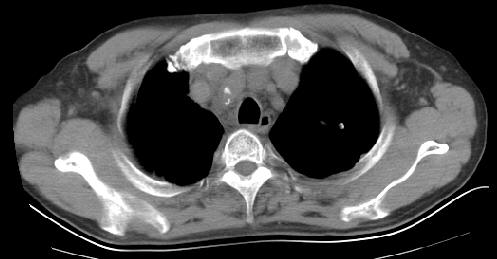

以下是引用草之原在2009-5-2 19:29:00的发言:[br]1.考虑右侧中心型肺ca纵膈淋巴结转移,双侧胸腔积液及右侧叶间裂积液,心包积液。[br]2.两肺上叶病灶,纵膈窗显示部分病灶硬化,考虑:结核。[br][br] [br]

以下是引用ct诊断高手在2009-5-2 19:08:00的发言:[br]我考虑右侧中央型肺癌 伴右肺节段性不张,两肺及纵隔淋巴结转移,右侧胸腔积液。

以下是引用zjzjr在2009-5-2 20:16:00的发言:[br]肺结核,转移瘤.纵隔淋巴结转移或淋巴瘤,右侧包裹性积液、斜裂积液。心包积液。